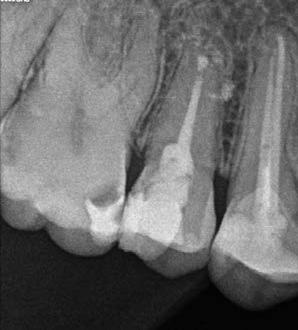

Nagyon fontos, hogy már a kezelések elején meghatározzuk, hogy melyek azok a hiányzó fogak, amelyeket a későbbiekben pótolni szeretnénk, valamint helyesen diagnosztizáljuk a kariológiai, endodonciai vagy parodontológiai okok miatt ellátást igénylő elváltozásokat. Szintén kiemelt jelentőséggel bír a fogak megtarthatóságának kiértékelése. A kezelési terv felállítása során tisztában kell lennünk azzal, hogy mely fogak alkalmasak fogpótlások ideiglenes vagy végleges elhorgonyzására.

A preprotetikai fázisban el kell látnunk a diagnosztizálásra került kórfolyamatokat, megfelelő pozícióba kell állítanunk a megtartani kívánt fogakat, pótolnunk kell az elvesztett csontállományt, valamint gondoskodnunk kell az íny megfelelő állapotáról. Ha szükség van rá, úgy a foghiányok pótlására szolgáló dentális implantátumok is ebben a fázisban kerülnek behelyezésre. Általánosságban elmondható, hogy azokat a kezeléseket, amelyek befejezése biológiai okok miatt hosszú időt vesz igénybe (pl.: fogszabályozás, csontpótlás, implantáció), a lehető leghamarabb érdemes elkezdeni.

A fogszabályzó kezelések egyik legfontosabb célja, hogy elérjük a lehető legharmonikusabb interokkluzális fogérintkezéseket, továbbá az állcsont relációs helyzetének frontális és szaggitális síkban is megfelelőnek kell lennie. A fogszabályzás befejezésekor a fogpozícióknak nem orthodonciai, hanem protetikai szempontok szerint kell ideálisnak lenniük. Az Invisalign ClinCheck szoftver (Align Technology) segítségével a protetikus az orthodontussal együtt meg tudja határozni azokat a végső fogpozíciókat, amelyek a lehető legjobb végeredmény biztosításához elengedhetetlenek. Bizonyos klinikai paramétereket, mint a fogak klinikai koronájának nagyságát, az egyes fogak fogíven belüli optimális pozícióját, a fogívek egymáshoz viszonyított helyzetét, a fogak között látható rések nagyságát, a frontfogak tengelyének dőlését, az overjet és overbite mértékét már a kezelések megkezdése előtt pontosan definiálni kell. Ezeket az adatokat viszont csak a tervezett végleges fogpótlás ismeretében lehet meghatározni, ezért van szükség az orthodontus és a protetikus szoros együttműködésére.